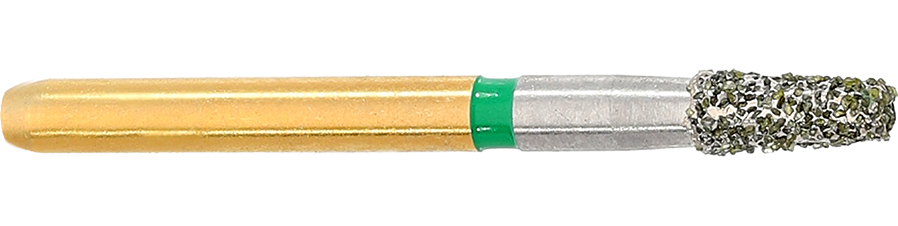

S6845KR - Inlay/Onlay & Cavity Preparation

S6845KR - Inlay/Onlay & Cavity Preparation

Modified Taper – Inlay/Onlay and Cavity Preparation

Application: Cavity Preparation | Inlay/Onlay Preparation

Structured diamond instruments (S-Diamonds)

Coarse grit for effective material removal

Faceted structured blank to reduce clogging and heat generation

Rounded edges (KR marking) to prevent micro-cracks

Komet’s S-Diamonds are designed to simplify cavity opening and initial preparation for inlay and onlay restorations. Featuring a structured diamond blank and coarse grit, these instruments deliver rapid and efficient substance removal while reducing heat and preventing clogging. Their rounded-edge design (KR) ensures safer preparation by minimising micro-cracks, making them the perfect choice for gentle yet effective treatments.